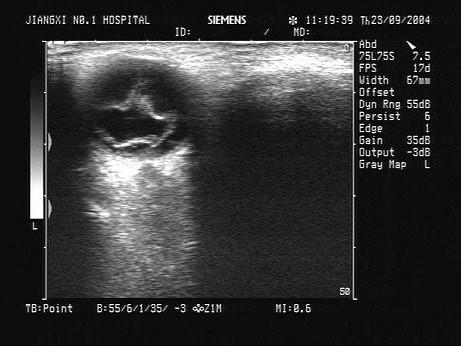

问题 某近视患者,眼部碰伤后,视物不清。眼部超声如图,最可能的诊断为?(?)

选项 A.视网膜完全脱离 B.视网膜局限性脱离 C.眼内异物 D.玻璃体血块 E.以上均不对

答案 A